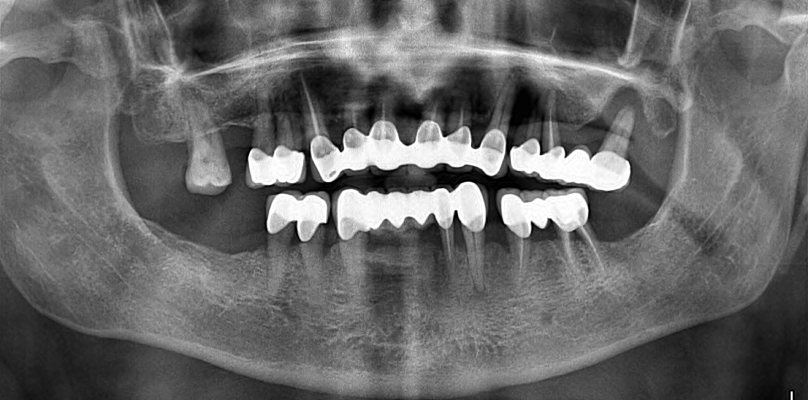

La première étape du processus de traitement consiste à prendre des images radiographiques détaillées. Ces images aident à déterminer le plan de traitement le plus approprié en évaluant la structure de votre mâchoire et votre santé dentaire. Nos radiographies révèlent à quel point le processus de traitement est extrêmement minutieux.